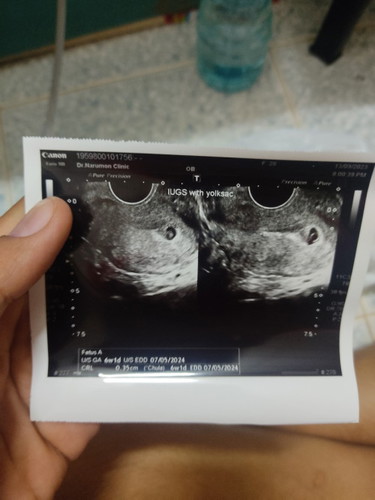

ท้อง 6วีค ตัวอ่อน ขนาด 0.35cm แต่เห็นหัวใจกระพริบแล้ว มีเลือดออก หมอยังไม่รับฝากครรภ์

ตอนไปฝากและอัลตร้าซาวด์ค่ะ6วิค1วัน ตอนนี้ครบ8วิคแล้วค่ะ

6wเหมือนกันเลยค่ะ พรุ่งนี้จะไปซาวน์ดูน้องแล้ว

6wเท่ากันเลยค่ะ

6วิคของเรา